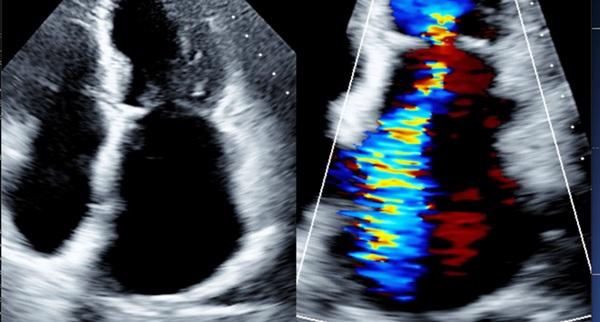

Photo Credit: Adapted from Asch FM. Atrial FMR primer: epidemiology, pathophysiology, imaging features, and clinical presentation. Presented at: TCT 2024. Washington, DC.